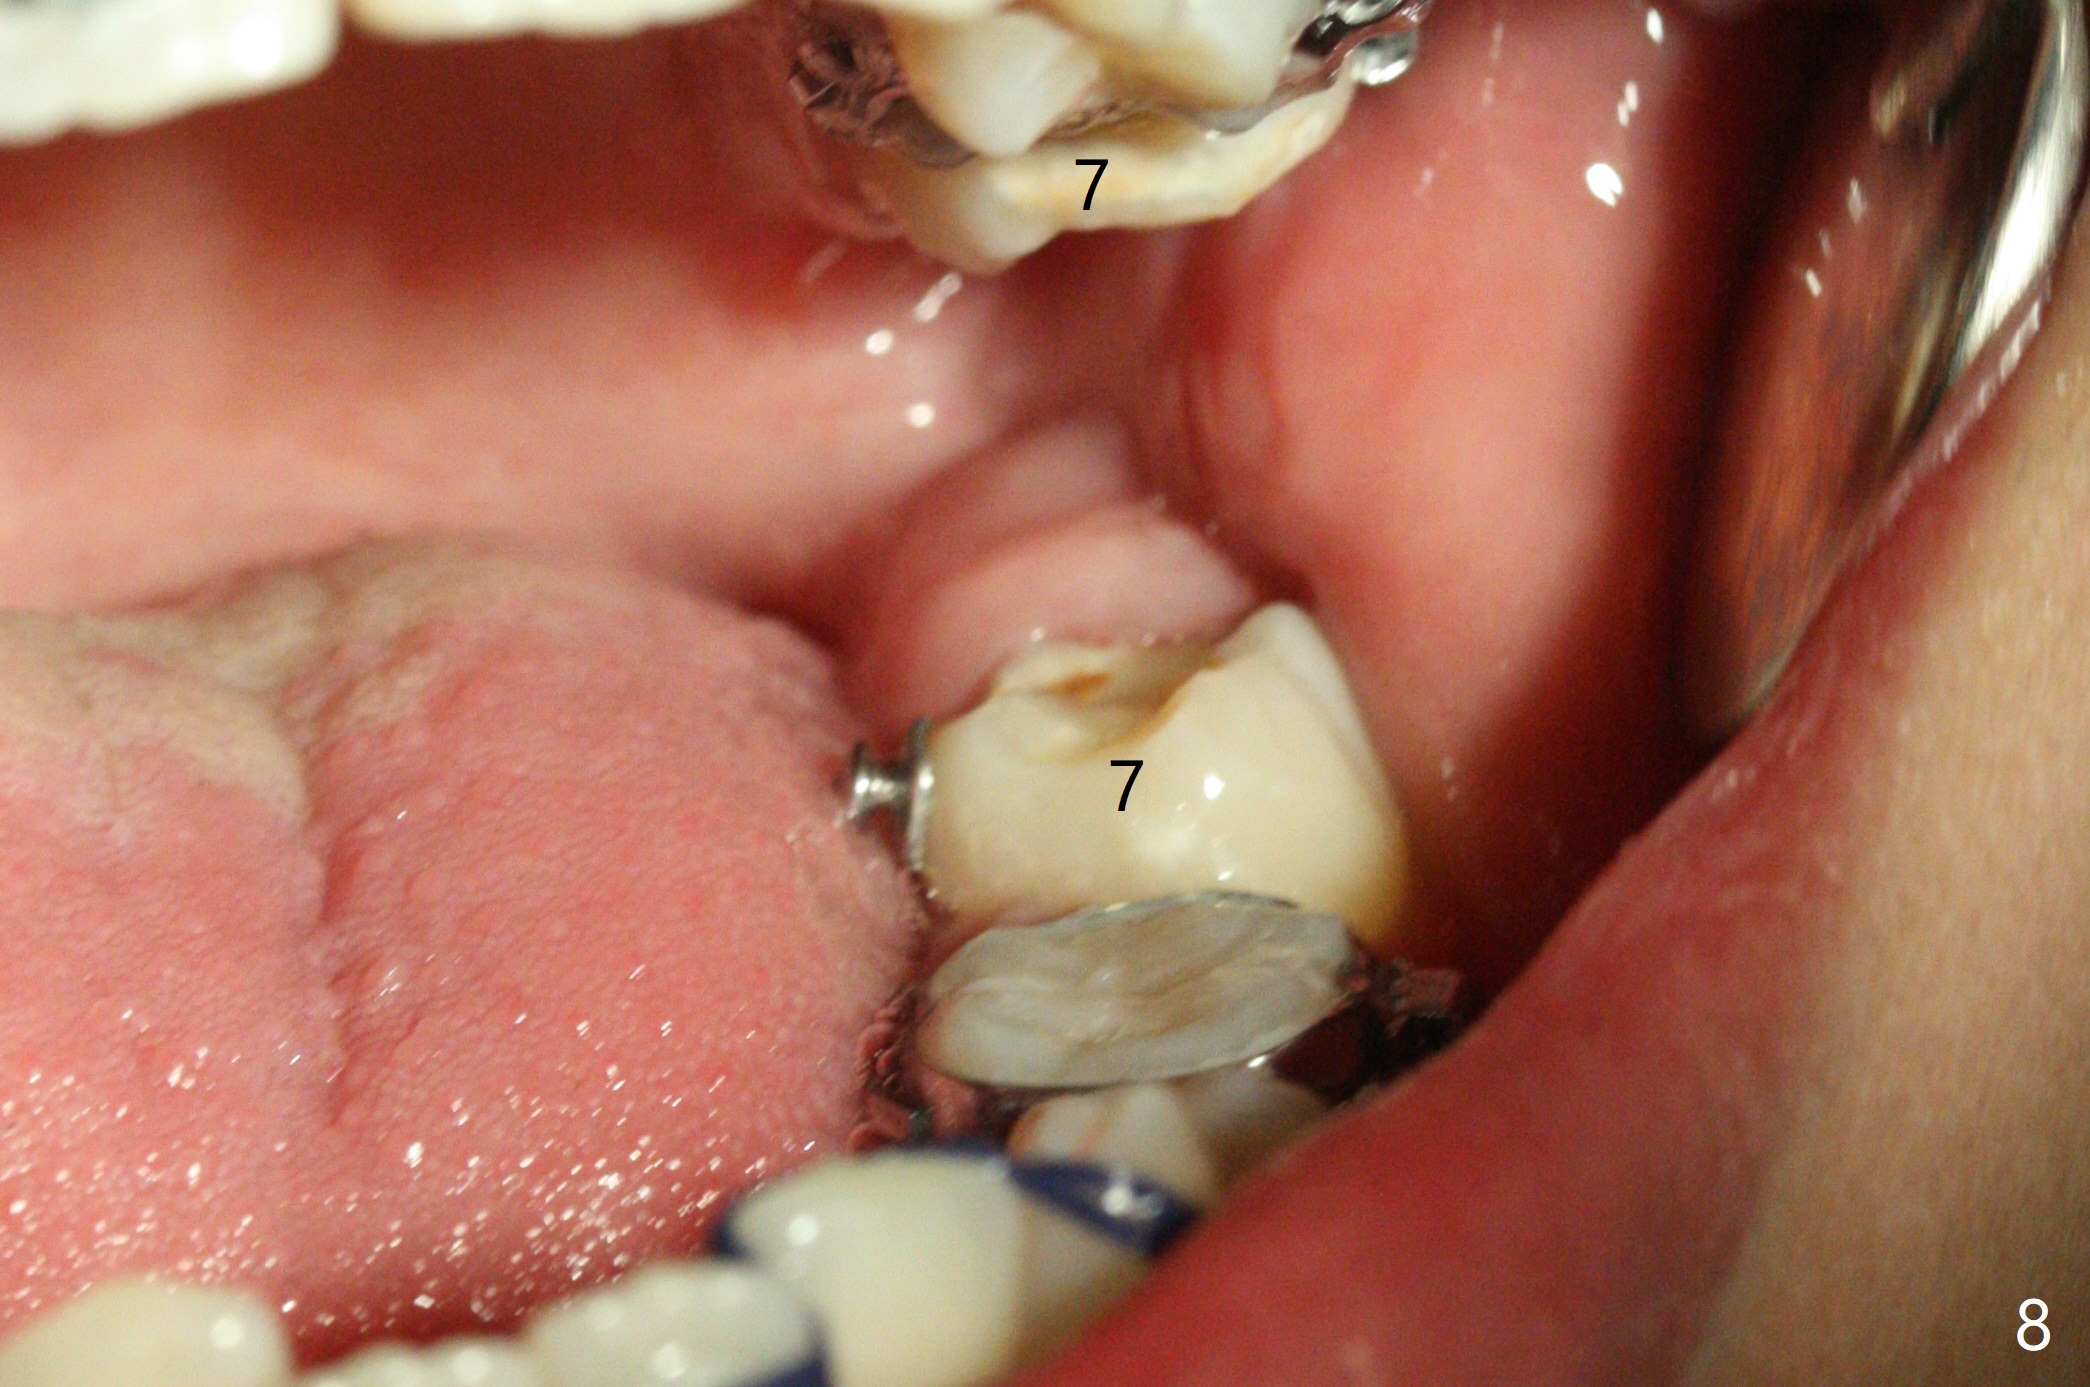

Three months post banding, the cross bite at 7s is corrected; with 7s' supraeruption and 6s' infraocclusion (because of occlusal composite (just removed), Fig.7,8), anterior open bite occur. Next visit place brackets in L7s with flexible wire. While 2 mechanisms are applied to gain more space for LR2 (Fig.9 *, ^), a special mechanism is utilized to correct LL2 cross bite (space gained). If the space for UR2 (Fig.10) is insufficient next appointment, what should we do? Otherwise, what should be done?